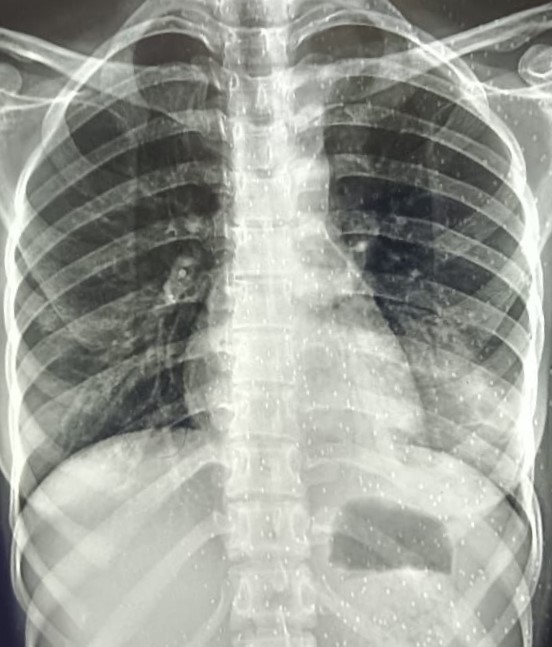

| 331 | IGGMC, Nagpur, Nagpur | P2 | 29-4141 | Madhukar Fulake | Consent taken on Paper | 55 Yrs. |

Provisional Diag : Post TB Sequelae, Fibrosis

Final Diag : Post TB sequalae, COAD With Left Sided Pleural Parenchymal Fibrosis With Left Sided Plural Calcification With Faty Liver |

Post TB Sequelae | Abnormality visible on x-ray |